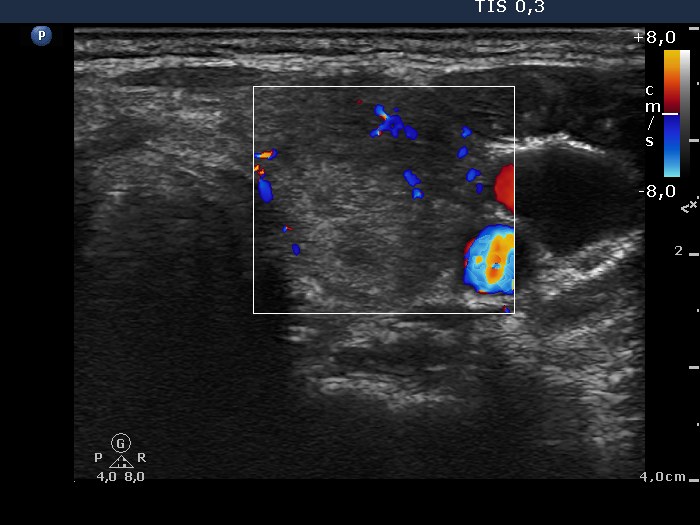

Subacute granulomatous thyroiditis - case 370 (ultrasonographic picture 6)

Left lobe, longitudinal view, color Doppler mode. The vascularization is decreased.